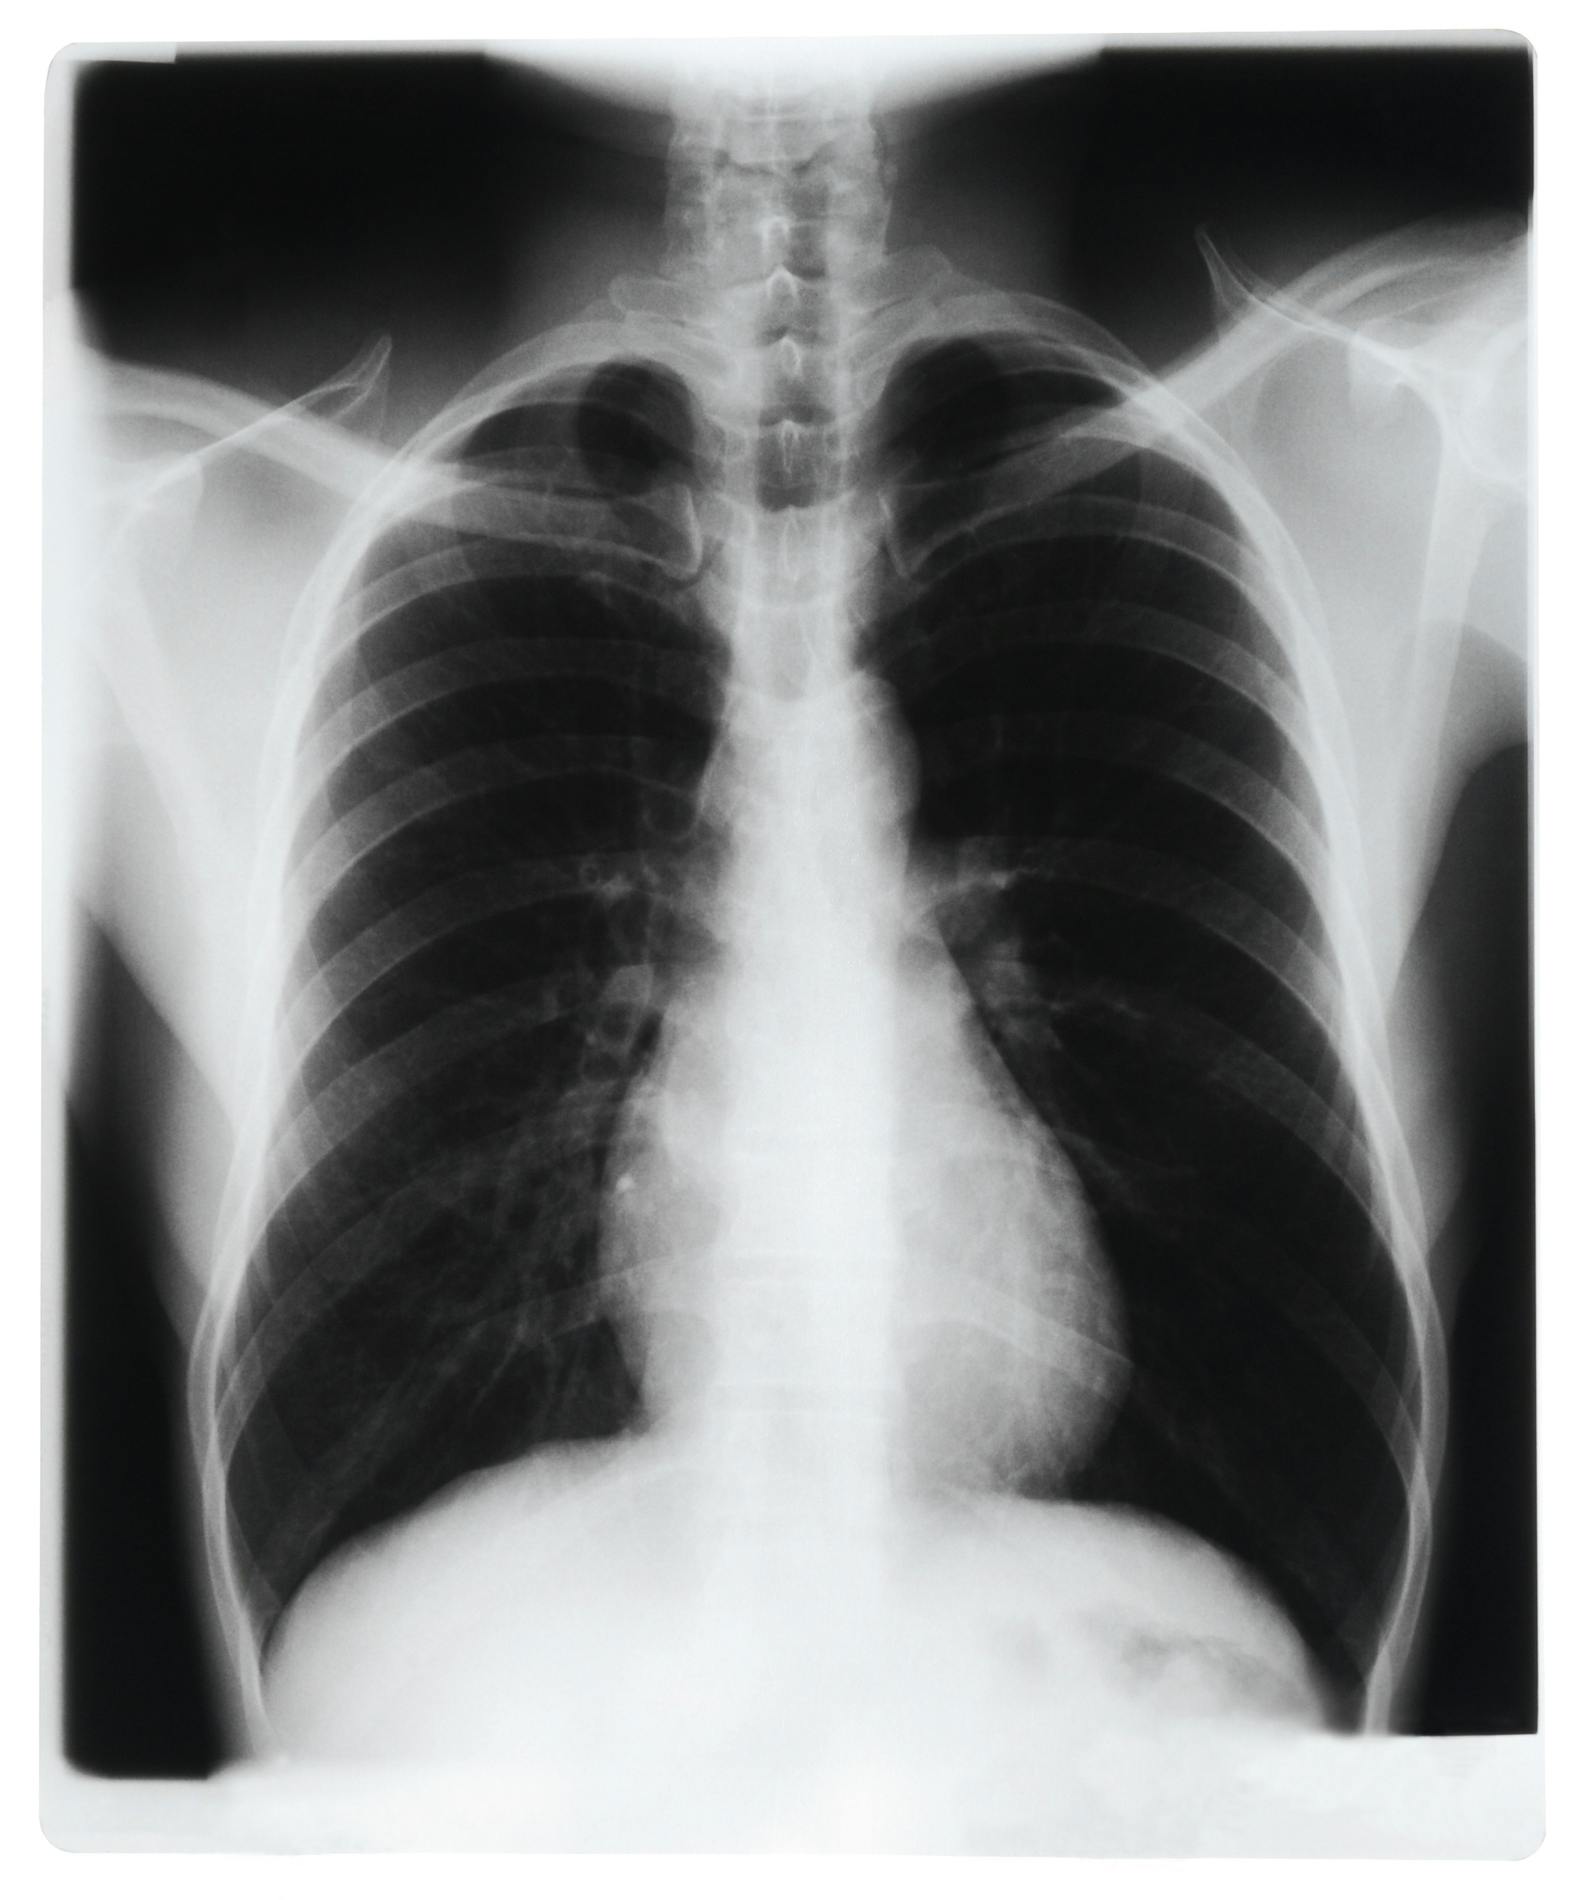

A new report in the Annals of Internal Medicine found that “shorter antibiotic treatment durations may be as safe and effective as longer ones for a small subset of patients hospitalized with community-acquired pneumonia (CAP).” CIDRAP has the news.

A team of researchers analyzed data from 67 Michigan hospitals from 2017 through 2014 to compare outcomes in CAP patients with shorter versus longer antibiotic courses. Only around 10% of the people hospitalized with CAP over the study period met the “eligibility criteria for short-course therapy, with most being excluded because of underlying comorbidities.”